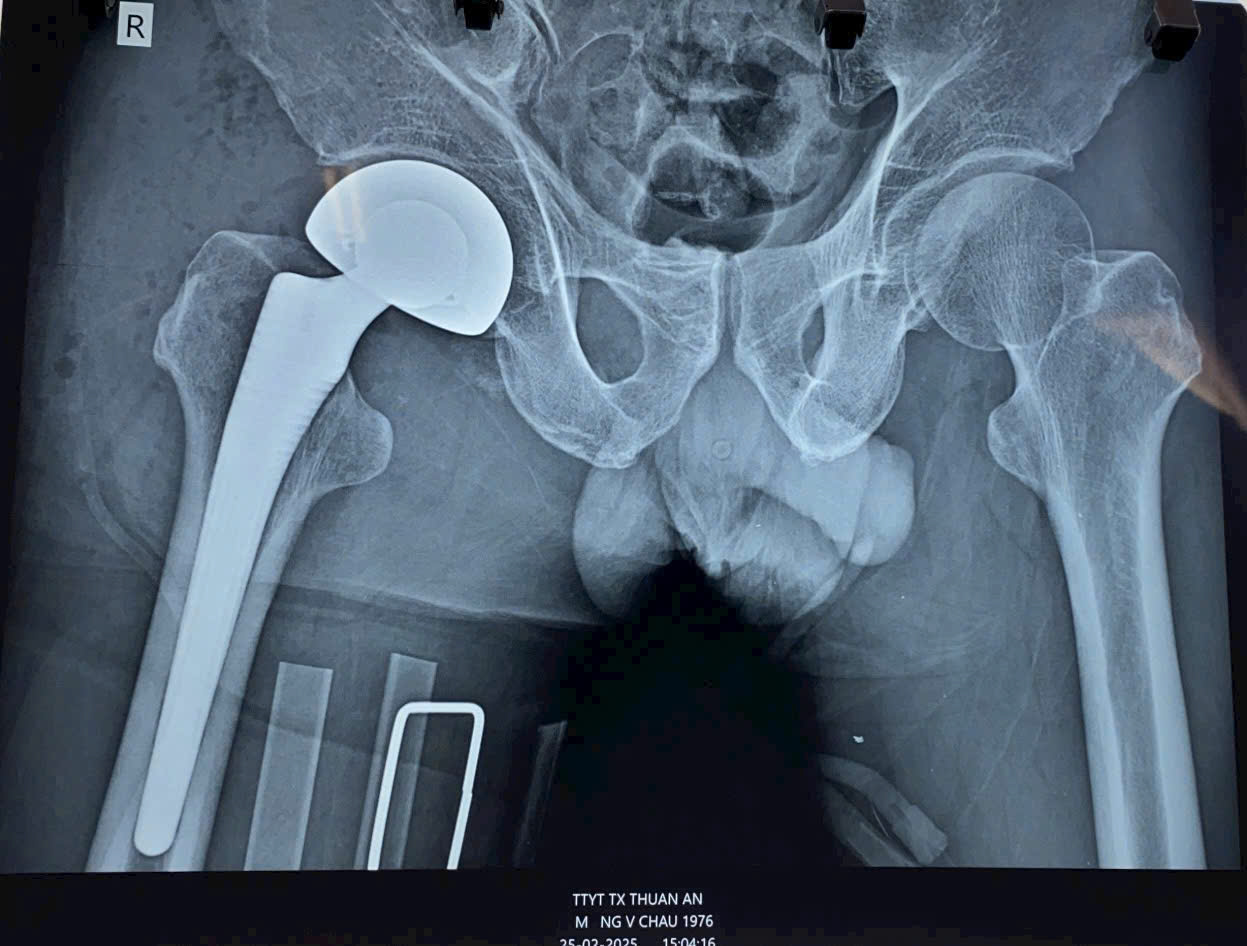

Ngày 25/02/2025, Trung tâm Y tế thành phố Thuận An, tỉnh Bình Dương đã triển khai thành công ca phẫu thuật thay khớp háng bán phần cho một bệnh nhân nam 50 tuổi bị gãy cũ cổ xương đùi phải. Đây là một bước tiến quan trọng, đánh dấu lần đầu tiên kỹ thuật này được thực hiện tại một trung tâm y tế tuyến huyện trong tỉnh Bình Dương.

Sau quá trình thăm khám và hội chẩn, các bác sĩ đã quyết định thực hiện phẫu thuật thay khớp háng bán phần nhằm giúp bệnh nhân phục hồi chức năng vận động và nâng cao chất lượng cuộc sống.

Ca phẫu thuật diễn ra thành công nhờ sự phối hợp nhịp nhàng giữa đội ngũ bác sĩ, điều dưỡng có chuyên môn cao cùng trang thiết bị hiện đại. Sau phẫu thuật, bệnh nhân có tiến triển tốt, dự kiến sẽ phục hồi vận động trong thời gian tới dưới sự hướng dẫn của đội ngũ phục hồi chức năng.